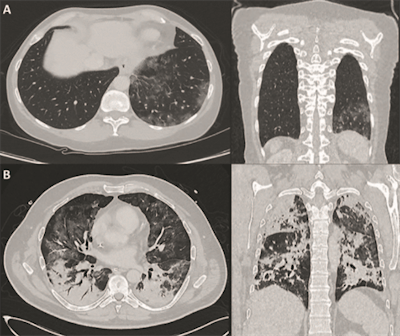

CT images of two patients with COVID-19 pulmonary manifestations. Incidental finding of SARS-CoV-2 infection in an asymptomatic 60-year old female (A) show peripheral ground-glass opacities in basal segments of the right lung. A polymerase chain reaction test confirmed SARS-CoV-2 infection on molecular level. A 51-year-old SARS-CoV-2-positive male (B) with pronounced bilateral pulmonary involvement of COVID-19 was hospitalized in an intensive care unit. Typical lesion spread to the center of the lungs and consolidation is present. Images courtesy of Nuklearmedizin.

CT images of two patients with COVID-19 pulmonary manifestations. Incidental finding of SARS-CoV-2 infection in an asymptomatic 60-year old female (A) show peripheral ground-glass opacities in basal segments of the right lung. A polymerase chain reaction test confirmed SARS-CoV-2 infection on molecular level. A 51-year-old SARS-CoV-2-positive male (B) with pronounced bilateral pulmonary involvement of COVID-19 was hospitalized in an intensive care unit. Typical lesion spread to the center of the lungs and consolidation is present. Images courtesy of Nuklearmedizin.FDG uptake patterns in other parts of a patient's body also can be attributed to COVID-19, which is known to damage the heart, kidneys, or bone marrow. Hence, whole-body PET could be used as a "noninvasive readout to assess [chronic] and concomitant organ damage," the authors wrote, citing a March 2020 report by Zou et al, which found FDG uptake in the bone marrow of one COVID-19 patient (Radiology, March 6, 2020).